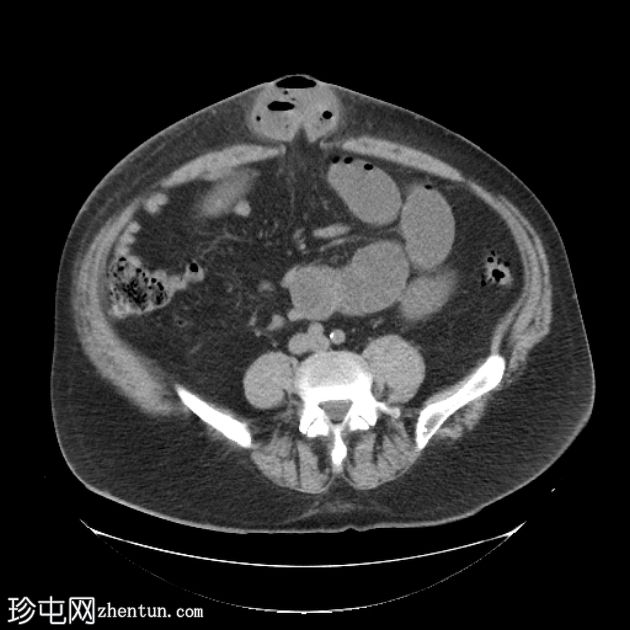

定位片

轴位

平扫

定位片显示多处扩张的小肠袢。侧位片显示脐部皮下透光区(脐疝)。

多处扩张的小肠袢内可见多个气液平面,直至进入脐疝的肠袢处可见移行点,而从疝口出来的远端小肠袢则呈塌陷状态。

诊断:嵌顿性脐疝继发急性小肠梗阻。